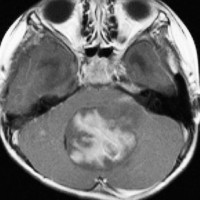

典型的な小脳虫部(小脳の真ん中)の髄芽腫です。横の方,ルシュカ孔へ伸びていないので上衣腫と区別できます。ガドリニウムという造影剤で白く写っています。